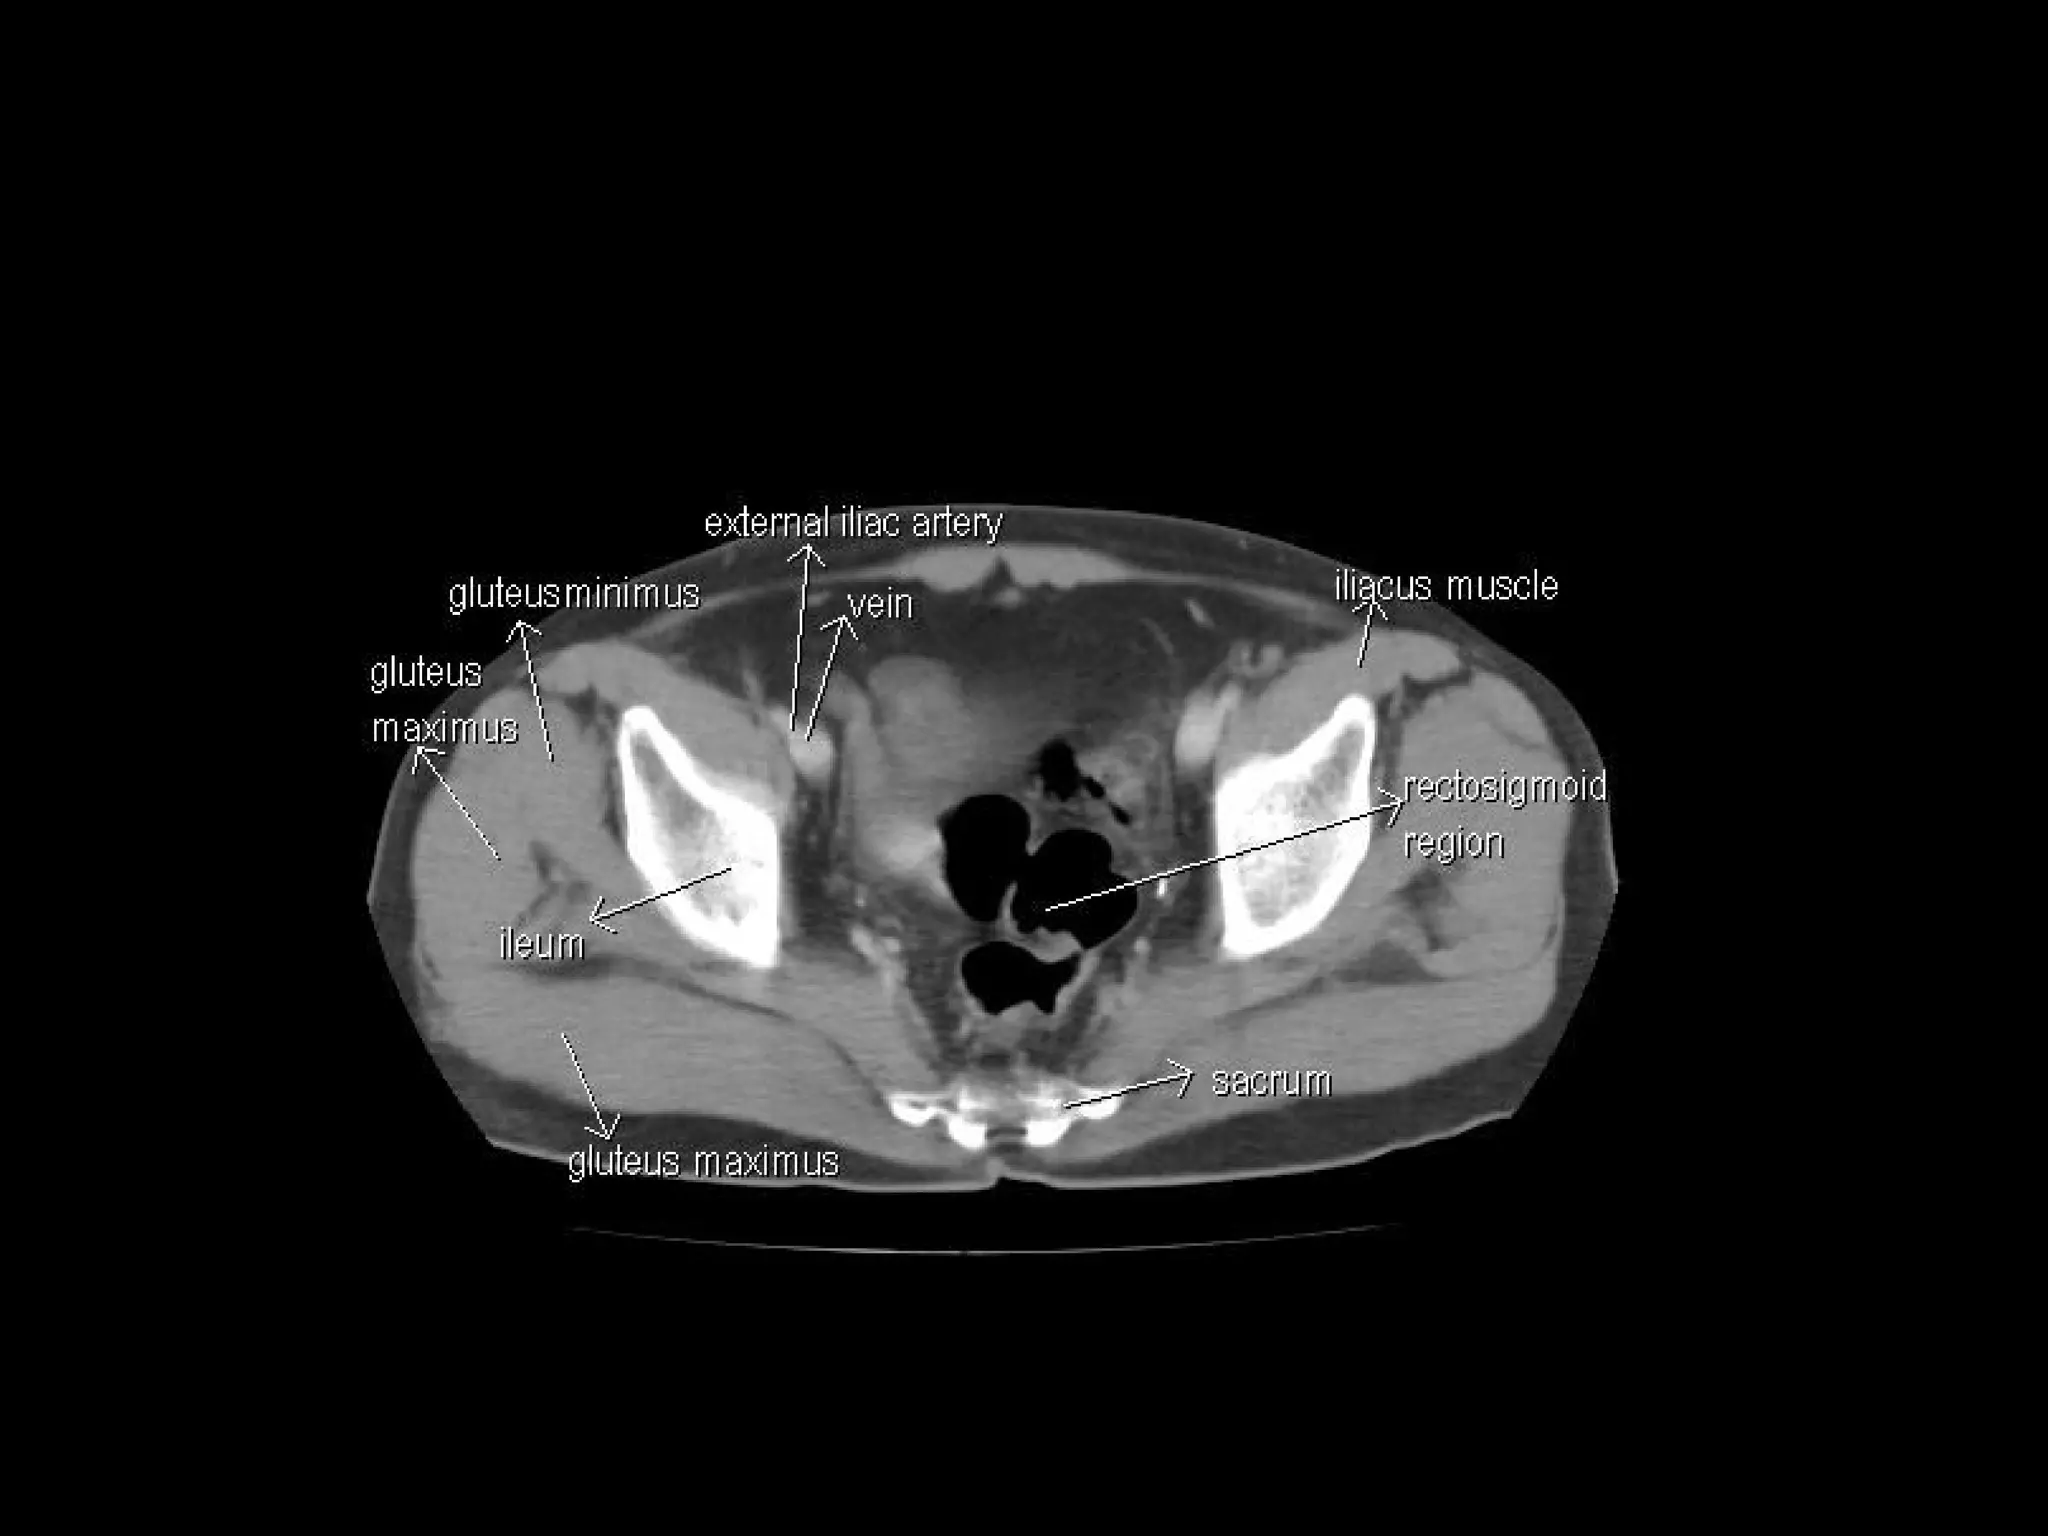

Radiographers are medical professionals who perform diagnostic imaging examinations and procedures to help physicians diagnose and treat diseases. They work under the supervision of radiologists to operate X-ray, CT, MRI, ultrasound and other medical imaging equipment and must have a strong understanding of human anatomy and pathology. Radiographers are responsible for correctly positioning patients, ensuring proper imaging techniques are used, and evaluating the quality of the resulting images.